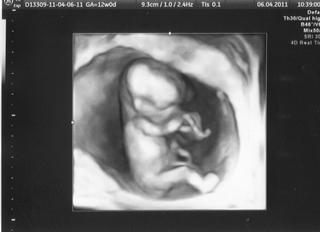

@katy31 jezis....ty mas nadhernu fotku!!!!!!!!!!!!!....moje babatko sa pred tyzdnom nechcelo moc ukazat, tak mam vsetko rozmazane......ale tyzden predtym som bola unesena, lebo som aj pupocnu snuru videla....